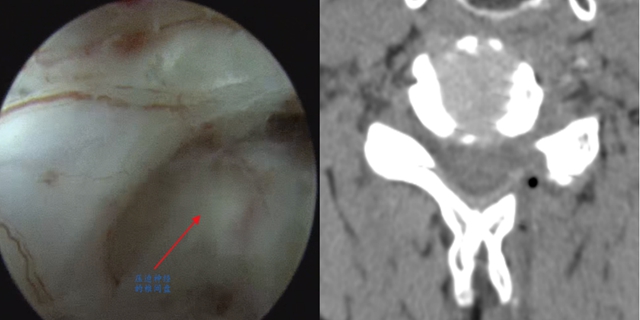

70歲的蔣先生1周前突然出現(xiàn)左上肢放射性疼痛,從頸部一直延伸到上臂,伴有麻木、無力感,于當(dāng)?shù)蒯t(yī)院針灸沒有改善后,來到骨傷科·脊柱骨腫瘤一組就診。經(jīng)戚力升主治醫(yī)師詳細(xì)檢查,結(jié)合影像學(xué)檢查,診斷為頸椎5/6節(jié)段椎間盤突出,突出的髓核壓迫神經(jīng)根,導(dǎo)致左上肢神經(jīng)癥狀。

術(shù)前

術(shù)后